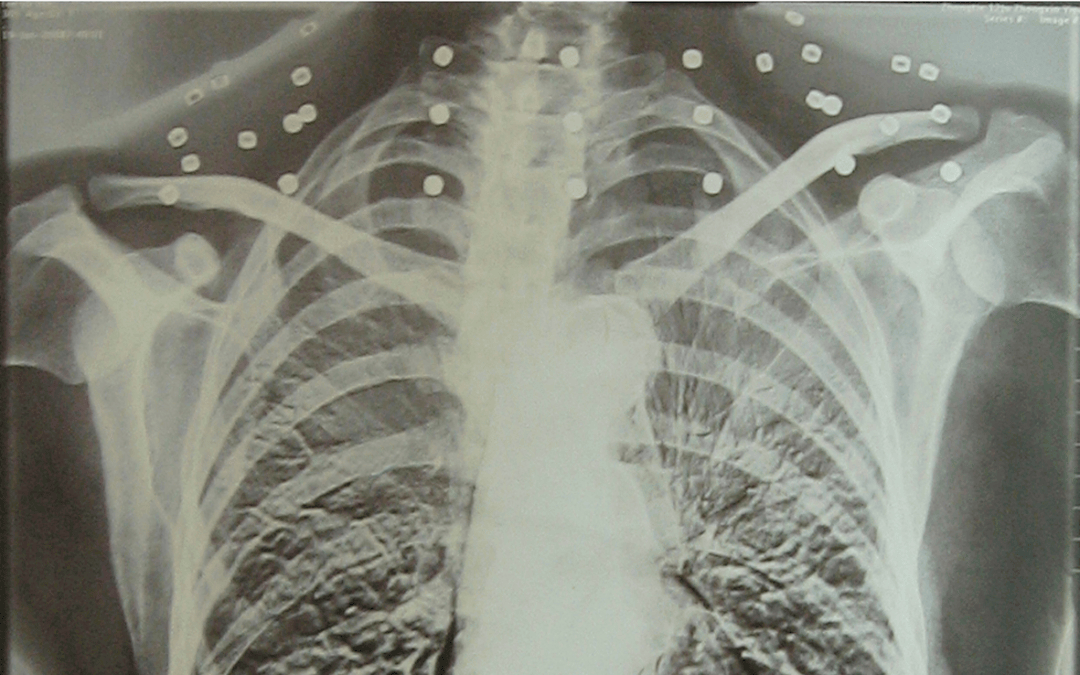

这张照片

是今年82岁的吴以先老人

拍摄的一张CT照

但实际上是

吴以先的颈部和腹部

共分布着33枚弹片

但是打进身体里的弹片

一直留在了体内

他体内的弹片都没有取出

这是他与战友并肩作战的见证

是他的勋章